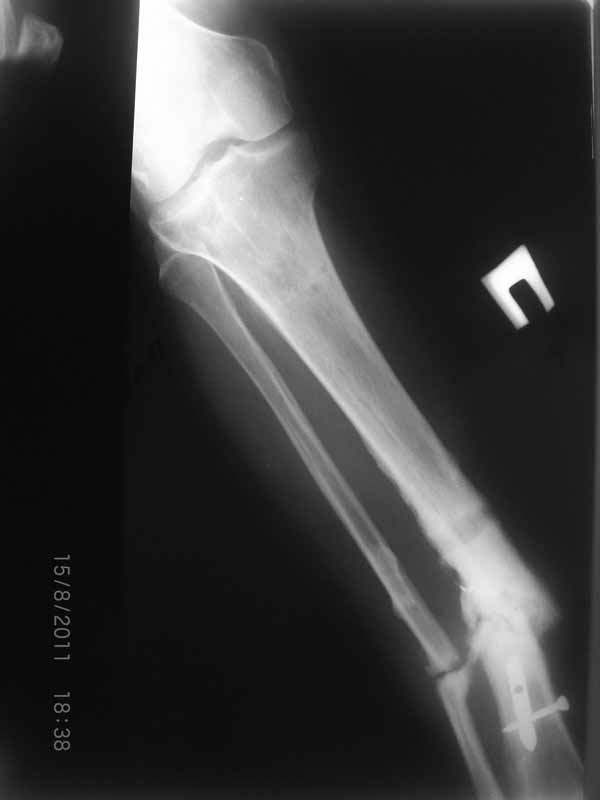

Первично у пациента травма в марте 2009г, когда в результате ДТП получил открытый оскольчатый перелом обеих костей правой голени на границе средней и нижней трети. При поступлении - скелетное вытяжение, затем по заживлению раны произведен остеосинтез пластиной. Со временем (точное время сказать затрудняется) пациенту разрешили полную нагрузку на конечность. Через год после операции пластина сломалась, в связи с чем пластина удалена и установлен интрамедуллярный гвоздь. Через 2 месяца разрешили полную нагрузку и гвоздь сломался. В сентябре 2010 произведено наложение спицевого компрессионно-дистракционного аппарата. В мае 2011 появилось отделяемое в местах проведения спиц, в связи с чем аппарат демонтирован. Правая голень временно иммобилизирована гипсовой повязкой, разрешена нагрузка на правую нижнюю конечность. После снятия повязки - клиника ложного сустава обеих костей правой голени. В настоящее время отмечается угловая деформация правой голени на границе средней и нижней трети с отклонением оси в медиальную сторону. Кожные покровы изменены за счет трофических нарушений(имеют более темную окраску по сравнению со здоровой ногой)На коже рубцы на месте проведения спиц.Движения в коленном и голеностопном суставах в полном объеме безболезненны. Пульсация артерий на стопе отчетливая, выпадение чувствительности от третьего луча в латеральную сторону по тылу стопы.  В таком виде пациент оказался у нас. Рады выслушать предложения о тактике лечения.

Вложение не в текстовом формате было извлечено…

Url     : http://weborto.net:8080/pipermail/ortho/attachments/20110816/e165342b/attachment-0005.jpg